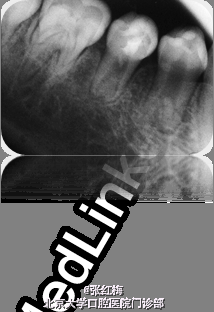

45牙合面充填体完好,边缘密合,叩痛(+),松I0,冷热测均无反应,舌侧牙根对应粘膜见1×1.2cm2 脓包扪诊有波动感,X线:发育8-9期,根中下1/3分成两根,根尖孔喇叭状,根尖周低密度影。

在牙髓再生术后1个月,3个月,5个月,9个月复查 1个月x线:45根尖周低密度影缩小,牙根继续发育。 3个月x线:45根尖周未见病变影,根周膜清晰,牙根继续发育。 5个月x线:45根尖周未见病变影,根周膜清晰,牙根继续发育。 9个月x线:45根尖周未见病变影,根周膜清晰,牙根继续发育,已近完成,髓腔缩小。 讨论:由于畸形中央尖一部分有髓角伸入,因此发现畸形中央尖应根据不同情况给予及时或相应处理。对于圆钝而无妨碍的中央尖可以不做处理。尖而长的中央尖容易折断或被磨损而露髓.可在麻醉和严格消毒下将此尖一次磨除。制备洞形,盖髓充填。还有一种方法树脂在牙尖周围加固防折,使畸形尖随牙齿一同发生生理磨耗,促使髓角形成修复性牙本质,可用于尚未建合的牙。短期内折断的畸形中央尖无牙髓根尖炎症状,且牙髓活力正常者,备洞盖髓充填。折断的畸形中央尖有牙髓炎根尖炎者,往往牙根未发育完成,需做根尖诱导形成术,或牙髓再生治疗。 牙髓坏死或者根尖炎年轻恒牙的牙髓治疗方法有:根尖诱导成形术,MTA根尖封闭技术,近年来的牙髓再生技术。 根尖诱导成形术,所用根管内充填材料是氢氧化钙及其制剂,诱导根尖周的组织在根尖部形成钙化屏障。需要多次复诊和更换根充药物,疗程较长,增加了根管再次污染的可能性,并不是所有都能形成根尖部的钙化封闭。而且根管壁仍然薄弱,增加了远期根折的风险。 MTA具有良好的生物相容性和封闭性,MTA根尖封闭技术中用其特性封闭根尖,防止充填材料在根尖部的外溢。生物相容性好,可以诱导矿化,但其完全固化需要较长时间,不易操作,抗菌效果不确定,价格昂贵。 牙髓血管再生术通过在操作中彻底有效的根管消毒,尽量保护牙髓干细胞和牙乳头间充质干细胞,并为这些干细胞的增殖和分化提供良好的环境,这些干细胞在信号分子和盖髓剂矿物三氧化物凝聚体(mineral trioxide aggregate,MTA)的诱导下,可以分化为成牙本质细胞和成牙骨质细胞等,从而在牙根继续发育中发挥着重要作用。研究表明,在坏死感染的年轻恒牙根管内进行成功的血管再生后,其根尖周炎症能愈合且牙根得以持续发育,出现根尖闭合、根管长度增加及管壁增厚等,牙髓血管再生术有可能成为治疗年轻恒牙根尖周炎的新选择。